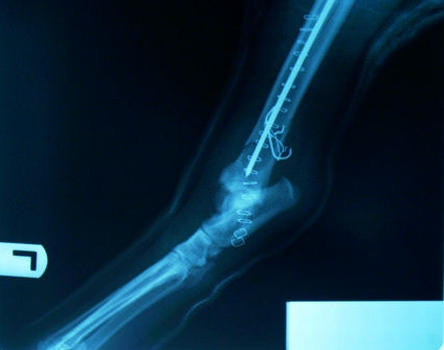

Here is a before and after picture of Otie's broken leg. It was a displaced fracture, but Dr. G was able to get good alignment and is very hopeful the break will heal completely. It is just above the "ankle", which is a good place for a break, because bone grows better here than higher on the leg.

Before....and after.